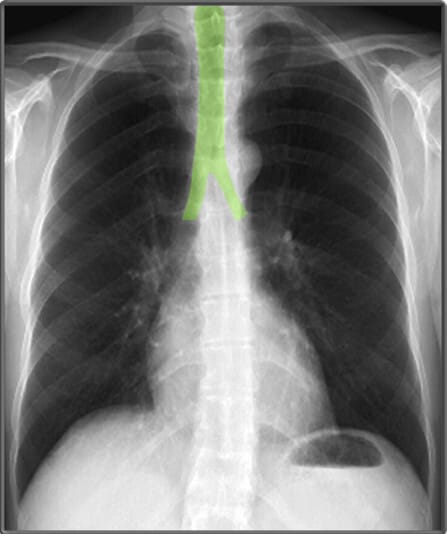

| 기관 (Trachea) |

| ✅ 정중앙에 위치해야 하며, 편위되어 있다면 종격동 이동(예: 무기폐, 기흉)을 의심해야 합니다. |